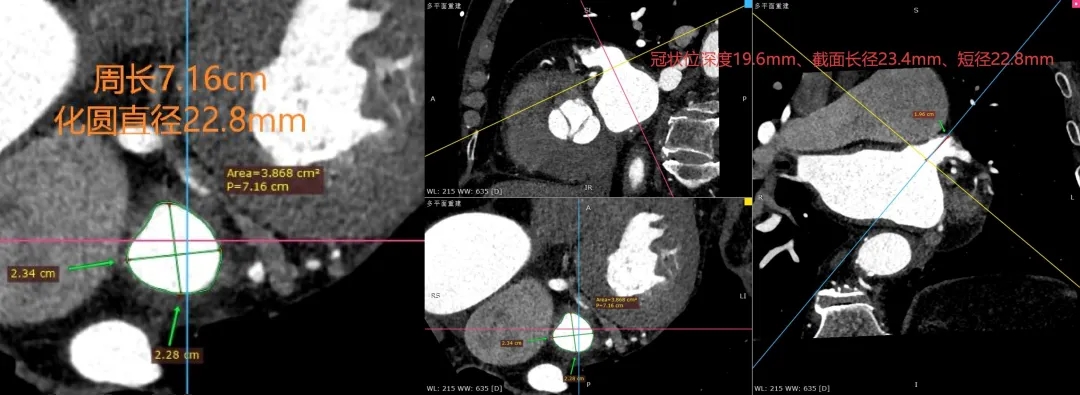

MPR数据测量

心耳最长径:23.4mm

心耳最短径:22.8mm

心耳深度:19.6mm

周长:7.16cm

化圆直径:22.8mm

该心耳为菜花型左心耳,开口类圆形;

开口MPR周长7.16cm,化圆直径22.8mm;CT测量深度在18-22mm(CT深度往往比DSA造影小4-5mm);